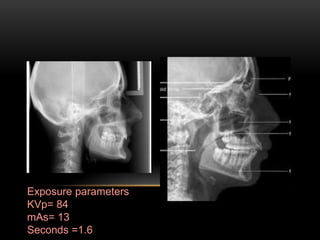

LATERAL CEPHALOMETRIC

PROJECTION

Film position - cassette is

placed perpendicular to the floor

with long axis of the cassette

placed vertically.

Position of patient - left side

of the face is positioned against

the cassette. Mid sagittal plane is

perpendicular to the floor and

parallel to film.

Central ray - perpendicular to

the film.

Exposure parameters

KVp= 84

mAs= 13

Seconds =1.6

INDICATIONS

• To evaluate facial growth and

development, trauma, disease and

developmental anomalies.

• Demonstrates the bones of the face,

skull as well as the soft tissue profile

of the face.